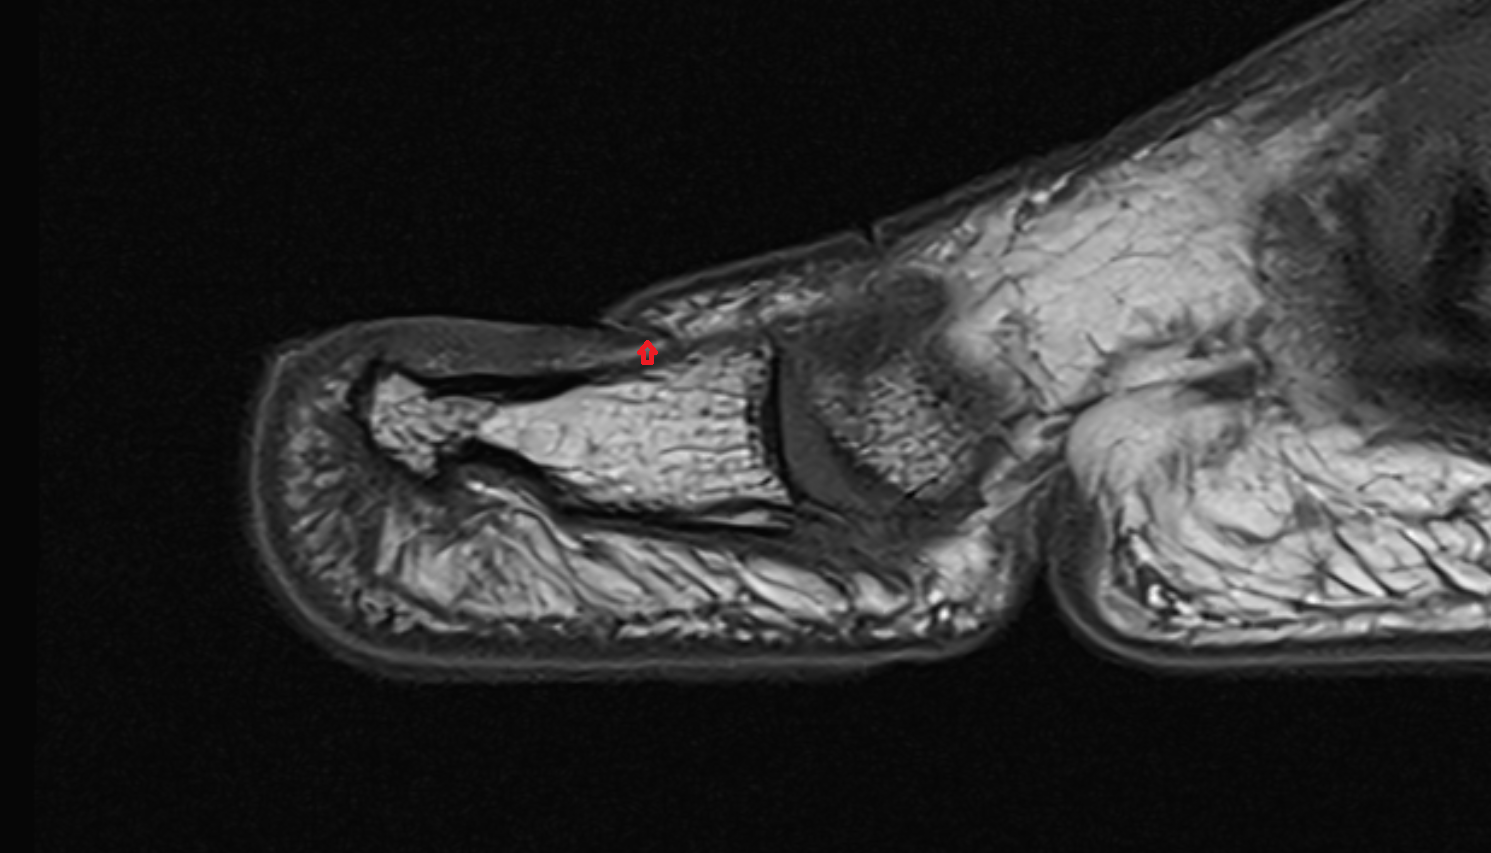

- Temporomandibular joint

- Mandibular condyle

- Mandibular fossa

- Articular disc of temporomandibular joint

- Articular eminence

- Attachment of inferior head of lateral pterygoid muscle

- Attachment of superior head of lateral pterygoid muscle

- Superior retrodiscal layer